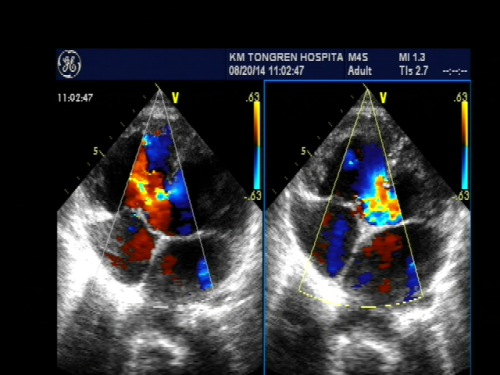

心脏超声是用超声波显示心脏、血管结构的一种检查方法,它分为M型超声、B型二维超声,三维立体超声。心脏超声由声波来探测血流状态和速度,还有彩色心脏超声由彩色血流的方向、压差表现不同的色彩变化,而知道病灶或异常构造的所在。此方法安全,没有放 射性,诊断准确率高,对病人没有痛苦和损伤,价格相对便宜,检查结果迅速及时,可反复多次检查,对很多心脏病的诊断有帮助。

动脉导管未闭